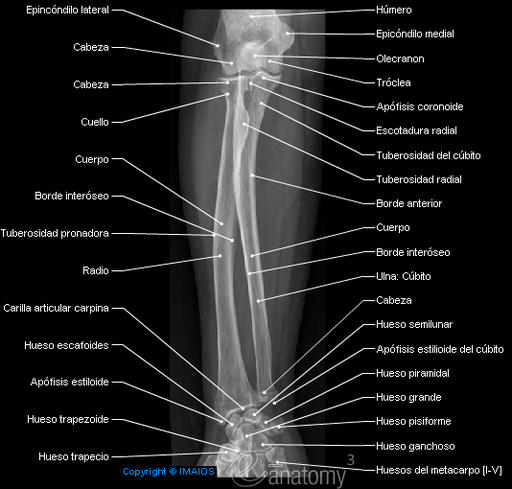

ANATOMIA DEL CODO Y ANTEBRAZO

CUBITO (ULNA) Y RADIO

ANATOMIA DEL ANTEBRAZO

CÚBITO

El cubito es el hueso interno o medial del antebrazo.

Epífisis proximal.

- Olécranon: apófisis dirigida hacia arriba, en su cara posterior, que constituye la prominencia dorsal del codo.

- Apófisis coronoides: apófisis dirigida hacia delante, en su cara anterior.

- Cavidad Sigmoidea mayor: es una cavidad articular abierta hacia delante que se encuentra entre las dos apófisis anteriores. Aquí se articula con la tróclea humeral.

- Cavidad sigmoidea menor: es otra cavidad que sale desde la anterior hacia la parte externa o radial del cúbito para articularse con el radio.

- Cuerpo o diáfisis: ligeramente curvado y más voluminoso por arriba que por abajo.

Epífisis distal: Es más pequeña y menos voluminosa.

- Cabeza del cúbito: que se articula con el radio.

- Apófisis estiloides del cúbito: es una prolongación hacia abajo que se conoce como el hueso redondeo de la muñeca que se puede palpar en su cara dorsal.

RADIO

Es el hueso más externo del antebrazo.

En la epífisis proximal tenemos la cabeza del radio. Es una superficie redondeada y plana, que se articula en su cara superior con el cóndilo del húmero y en su cara interna con el radio.

A continuación y hacia abajo sobresale una zona llamada TUBEROSIDAD BICIPITAL (donde se inserta el bíceps).

En la epífisis distal hay una superficie articular en la cara interna para unirse a la cabeza del cúbito, y otra superficie articular en su cara inferior para articularse con el carpo. En esta cara inferior existe una prolongación hacia abajo llamada APÓFISIS ESTILOIDES DEL RADIO (menos sobresaliente que la del cubito).